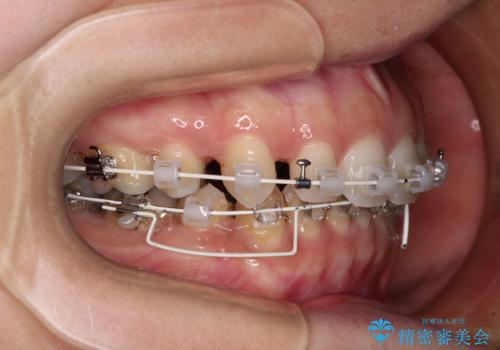

- 審美装置

上下左右第一小臼歯4本を抜歯し、ワイヤー装置にて口元を引っ込めるよう矯正治療を行うこととしました。

奥歯が前方に傾斜していることで深く咬みこむ(ディープバイト)状態であったので、なかなか抜歯したスペースが閉じず、様々な方法でディープバイトを改善しながら治療を進めていくこととなりました。